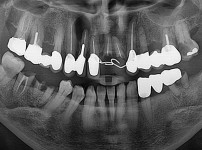

숙면임플란트 3개 - 스트라우만임플란트 (이*웅님)